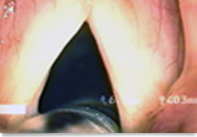

Activation of spasmodic dysphonia

Dr. Hyung-tae Kim, director of Yeson Voice Center, has presented his research paper revealing the causes of spasmodic dysphonia in the Acta Oto-Laryngologica, one of the greatest international journals for otolaryngology and head & neck surgery. This article is written by Dr. Hyung-tae Kim as ch…